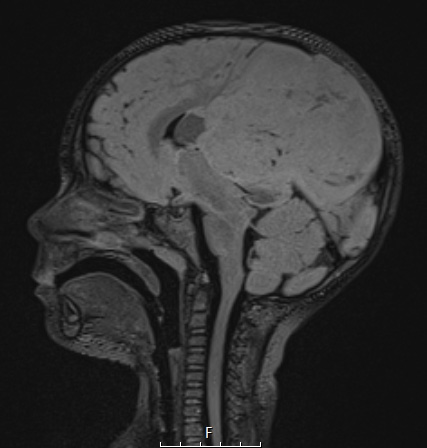

Case 1 History ---- The patient was a 3-year-old girl who presented with vomiting and altered mental status for 2 days which progressed to unresponsiveness. MRI demonstrated a “large left parietal mass measuring up to 9.7 cm with marked mass effect and involvement of the left parietal bone”. Operative procedure: craniotomy with tumor excision. ---- 1A1-5 MRI studies ---- 1A 1This FLAIR scan shows an enormous isointense mass with focal hypointensities.